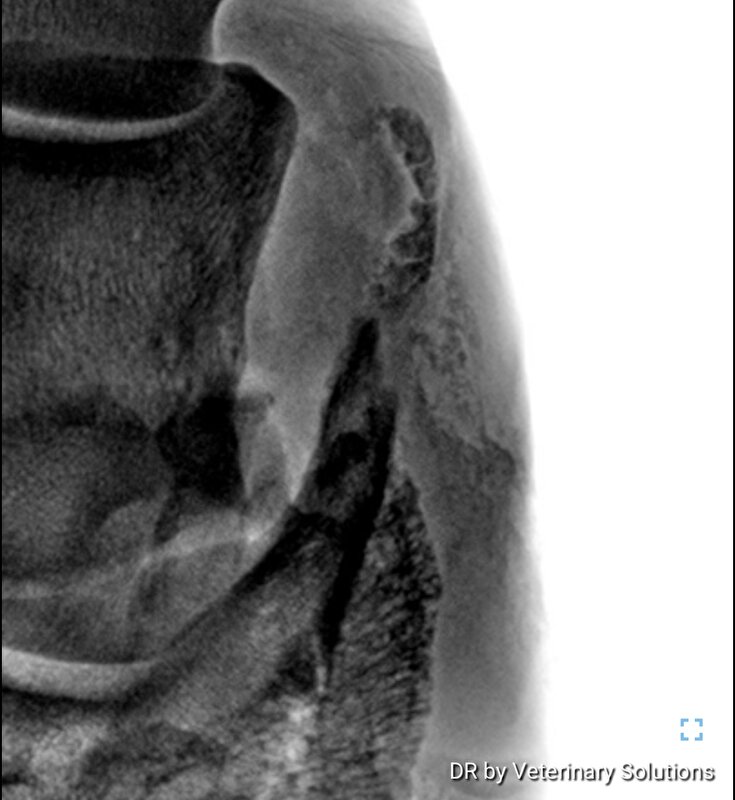

zefiros schreef:Hier best erge verbening vh hoefkraakbeen beide hoeven.